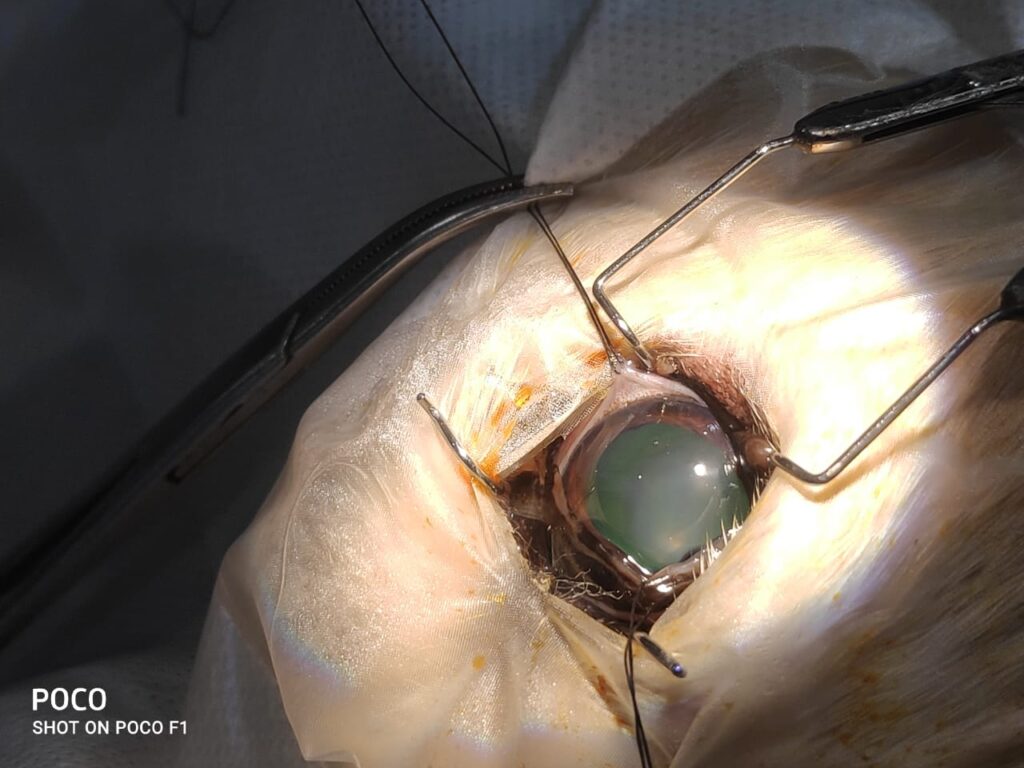

In dog with diabetes, cataracts develop very fast and they can lead to medical and surgical emergency. Once a lens has developed a cataract, it should removed surgically. cataract surgery is extremely delicate surgery and is performed under general anesthesia with high-magnification using an operating microscope. Some dogs require anti-inflammatory medication for several weeks, months, or lifetime following cataract surgery.

Phaco surgery

Cataract surgery is performed using a process called phacoemulsification. Phacoemulsification uses an instrument to deliver ultrasonic energy to the cataract. Break up of the cataractous material occurs so that it can be aspirated from the eye. A very small incision is made into the cornea to allow the instrument into the eye. An artificial lens is then generally placed in the eye where the cataract used to be (in some instances placement of an artificial lens is not possible, but in these cases vision is still better than it is with a cataract